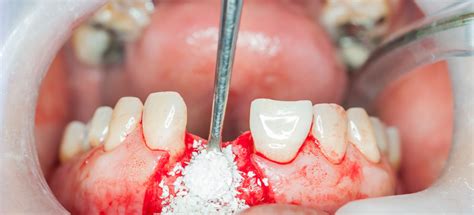

Un injerto de hueso dental es un procedimiento de implantación de un fragmento óseo en el maxilar o la mandíbula para aumentar su volumen. De este modo, incrementamos la cantidad de hueso y consolidamos el soporte sobre el que luego colocaremos el implante dental.

El fragmento de hueso que vamos a injertar en la mandíbula o el maxilar puede tener diferentes orígenes. Se puede obtener:

- Del propio individuo: injerto autólogo, autógeno o autoinjerto.

- De otro individuo de la misma especie: injerto aloinjerto.

- De otra especie animal: xenoinjerto.

- Por sintetización química, imitando alguno de los componentes del tejido óseo: injertos aloplásticos.

El empleo de un tipo de injerto u otro -a veces se utilizan de manera combinada- va a depender de la situación clínica y de las preferencias del cada profesional.

Sin embargo, es importante resaltar que el mejor injerto, el gold standard, es todavía el hueso autólogo o del propio paciente. Es el único con propiedades osteogénicas (creador de hueso), osteoconductoras (permite el crecimiento de hueso nuevo entre sus partículas) y osteoinductoras (estimula la diferenciación de células capaces de producir hueso en los tejidos adyacentes al injerto).

El hueso autólogo es especialmente importante para conseguir regeneraciones grandes y con componente vertical. Por otro lado, el hueso autólogo presenta la desventaja de que, al ser obtenido de otra zona (generalmente de otra zona del maxilar o de la mandíbula) provocamos una herida adicional a la del injerto, empeorando el postoperatorio del paciente.

En este caso, la utilización de técnicas regenerativas basadas en injertos, junto con la utilización de proteínas derivadas de la matriz del esmalte, ofrecen la posibilidad de revertir esta pérdida ósea. Al menos menos parcialmente. Para ello, el cirujano bucal rellena con hueso los defectos presentes en la periferia del diente.